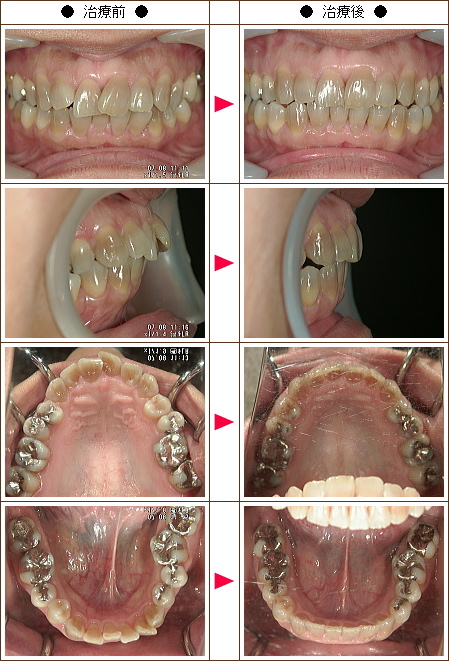

☆歯のデコボコ矯正症例[K.O様 42歳 女性]